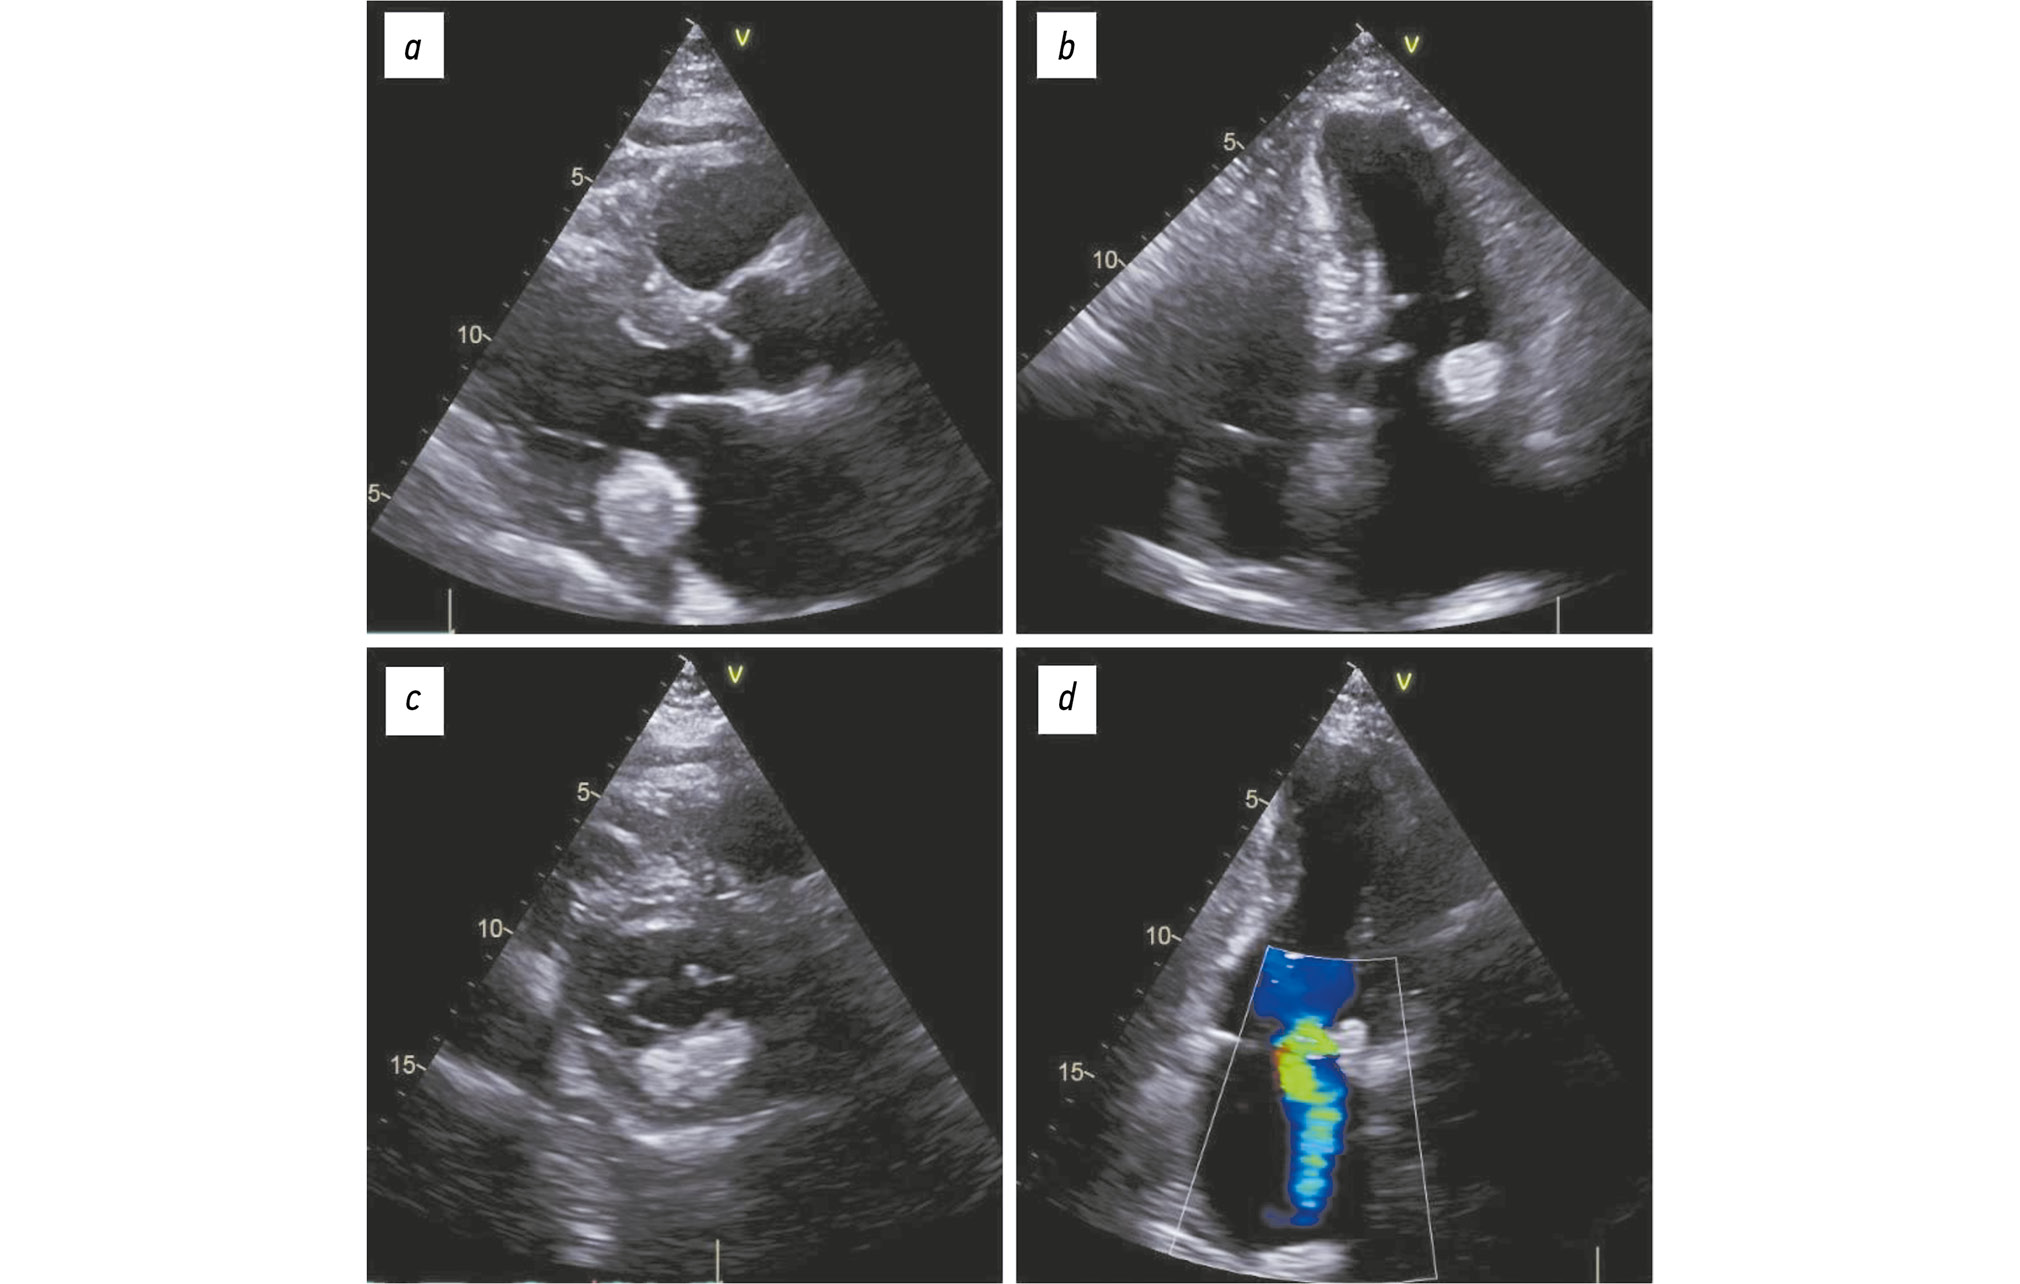

To further assess the nature of the lesion, electrocardiogram (ECG)-gated cardiac CT angiography was performed. It revealed an irregularly shaped lesion measuring 25 × 23 × 43 mm located at the base of the posterior mitral leaflet and within the left ventricular myocardium. The lesion exhibited peripheral calcifications with densities ranging from 1,335 to 1,350 HU and a central area of lower density (540–560 HU), with no contrast enhancement during either the arterial or venous phases. These findings were consistent with caseous subvalvular calcification beneath the posterior mitral leaflet (Fig. 2).

Fig. 2. ECG-gated cardiac computed tomography, clinical case 1: a–c, contrast-enhanced images, bone window; d, non-contrast image, soft tissue window; findings consistent with caseous subvalvular calcification beneath the posterior mitral leaflet: a, three-chamber view; b, four-chamber view; c, short-axis view at the mitral valve level; d, axial view.

CT also showed advanced coronary atherosclerosis, signs of scarring in the apical segments of the left ventricle, and left atrial enlargement. Medical therapy led to improvement the the patient’s coronary artery disease, and he was discharged with instructions for ongoing cardiology follow-up.